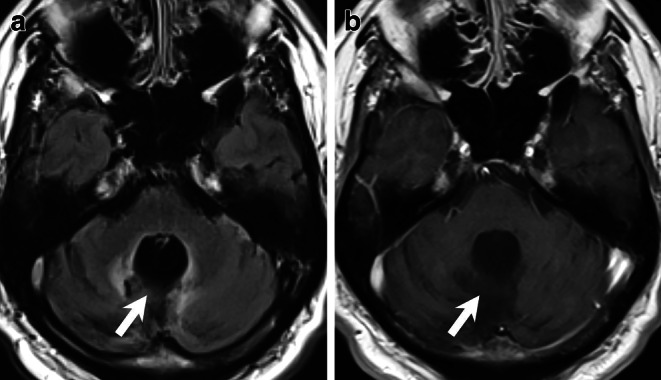

Abstract Image